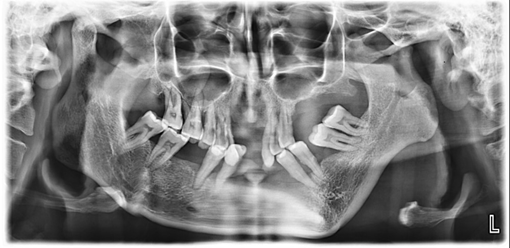

On investigation, an orthopantomogram (OPG) was advised. The radiograph reveals significant asymmetry of the mandible, with notable hypoplasia of the left condyle and a marked reduction in the vertical height of the left ramus. The left antegoinial notch appears prominently accentuated, suggesting altered mandibular growth. Despite these morphological changes, the cortical bone appears well-defined, with normal bone density and an intact lower border of the mandible. The glenoid fossa on the left side maintains a normal appearance, without evidence of dysplasia or displacement. In contrast, the right side of the mandible appears structurally normal (Figure 4).

Figure 4 Orthopantomogram showing mandibular asymmetry with hypoplastic left condyle, reduced vertical height of the left ramus, and a prominent antegonial notch. Cortical bone and mandibular border are intact with normal bone density. The left glenoid fossa appears normal; the right mandible is structurally unremarkable.

Radiographic imaging further supports the diagnosis. The orthopantomogram (OPG) reveals mandibular asymmetry, left-sided condylar hypoplasia, and a reduction in vertical ramus height, all of which are indicative of the mandibular underdevelopment typical of Nager syndrome.10 The prominent antegonial notch also points to abnormal mandibular growth, a finding frequently reported in these patients.17 Despite these skeletal changes, the well-defined cortical bone suggests that severe osteodysplastic conditions are unlikely.